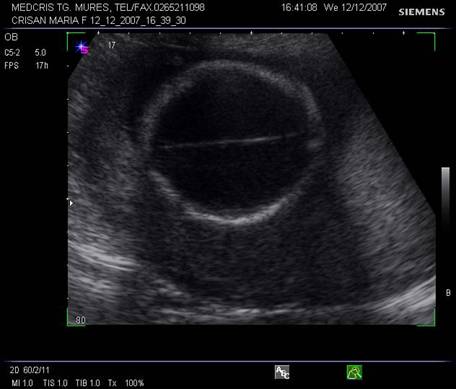

Fig. nr. 150. Planul II de sectiune transversala a craniului fetal.

Planul III sau planul frontooccipital, pentru masurarea diametrelor biparietal si frontoocipital. Ecoul de mijloc frontoocipital este intrerupt in zona cavum septum pellucidi, anecogena, situata anterior de ventriculul III. Acesta este situat intre doi nuclei talamici hipoecogeni si apare ca o despicatura mica sau o linie.